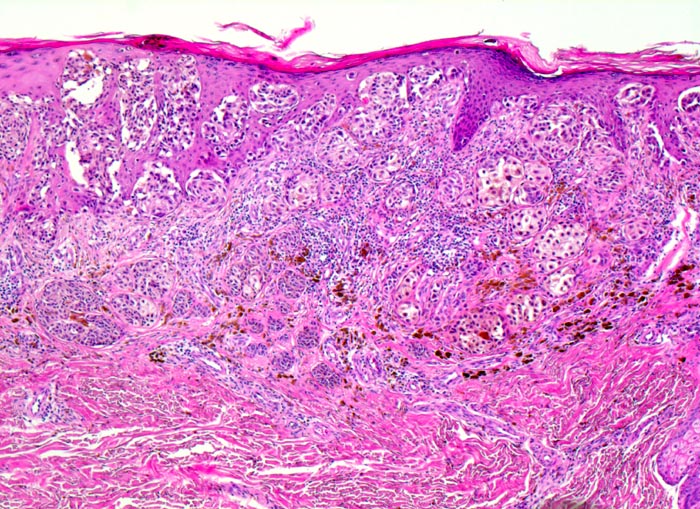

PathoPic – image database / PathoPic ID 3959 - oberflächlich spreitendes Melanom (SSM)

oberflächlich spreitendes Melanom (SSM)

Asymmetrischer melanozytärer Tumor bestehend aus auffallend grossen Zellnestern, welche zur Tiefe hin kaum an Grösse abnehmen und sich auch in oberen Anteilen der Epidermis ausbreiten.

Leicht erhabener scharf begrenzter brauner in der Mitte dunkelbraun gefärbter Bezirk, max. Dm 15mm Infiltration des Stratum papillare bis an das Stratum reticulare und einer max. Tumordicke von 1,12mm (pT2; Clark Level III).

Verdächtiger Nävus Kniekehle links.